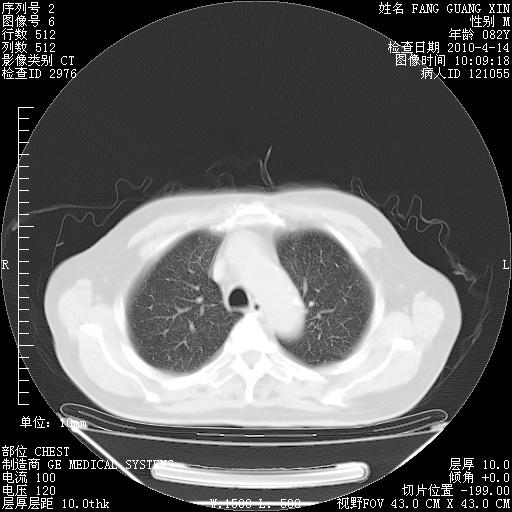

4月28日肺部CT——再次出现类似去年5月9日——透光度降低,(影像科认为)“间质性”改变。

4月28日肺部CT——再次出现类似去年5月9日——透光度降低,“间质性”改变。